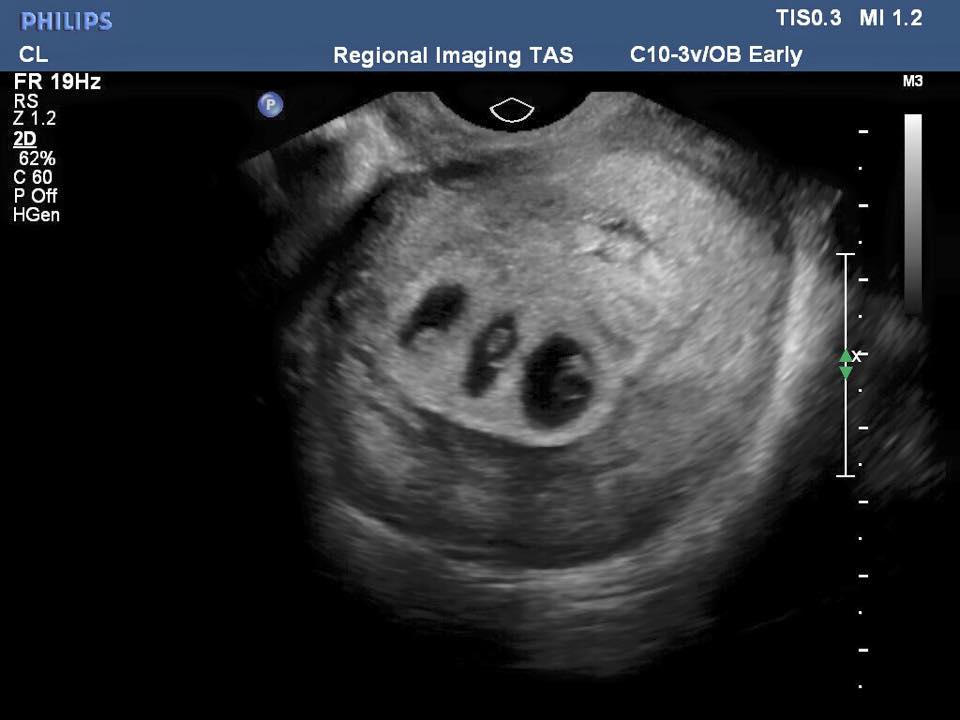

Az ultrahang megmondta a választ: a lány hármasikreket várt. Nemsokára a három fiú még még két fiútestvért és egy lánytestvért kap. A gyerekek és pár is nagyon örültek a jó hírnek, de a hír csak rövid ideig volt jó. Az ultrahang felvétel kimutatta, hogy a picik közül a kislány nem kapott elég oxigént.

A családnak most szörnyű döntést kellett meghoznia. Hagyják meghalni a kislányt, még a méhben, azért, hogy a két kisfiú egészségesen fejlődjön tovább és császárral megszülessenek, vagy indítsák be a szülést. Ha az utóbbit választják, mindhárom gyermek élete veszélybe kerül, de így megmenthetik a kislányt.